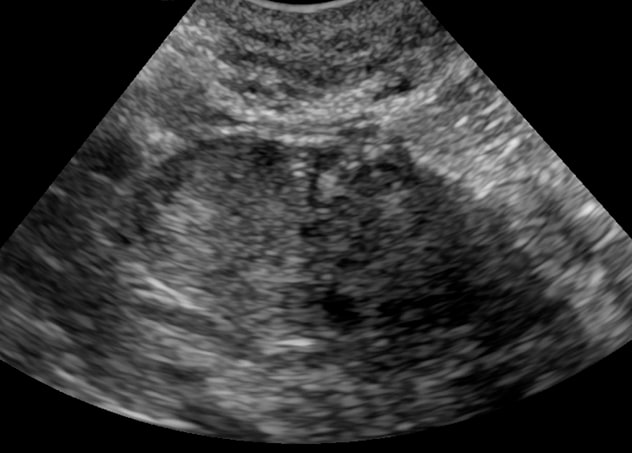

La ecografía pélvica muestra evidencia de tumor de células de Leydig en el ovario derecho.